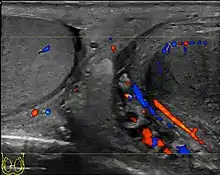

Epididymo-orchitis in a 77-year-old man. (a) Transverse sonography shows enlargement of the epididymis with hypoechogenicity noted over the testis and epididymis associated with scrotal wall thickening. (b) Color Doppler sonography showed hyperemic change of the testis and epididymis, presenting as an “inferno” vascular flow pattern.

Epididymitis and epididymo-orchitis are common causes of acute scrotal pain in adolescent boys and adults. At physical examination, they usually are palpable as tender and enlarged structures. Clinically, this disease can be differentiated from torsion of the spermatic cord by elevation of the testes above the pubic symphysis. If scrotal pain decreases, it is more likely to be due to epidiymitis rather than torsion (Prehn's sign). Most cases of epididymitis are secondary to sexually transmitted disease or retrograde bacteria infection from the urinary bladder. The infection usually begins in the epididymal tail and spreads to the epididymal body and head. Approximately 20% to 40% of cases are associated with orchitis due to direct spread of infection into the testis.

At ultrasound, the findings of acute epididymitis include an enlarged hypoechoic or hyperechoic (presumably secondary to hemorrhage) epididymis [Fig. 20a]. Other signs of inflammation such as increased vascularity, reactive hydrocele, pyocele and scrotal wall thickening may also be present. Testicular involvement is confirmed by the presence of testicular enlargement and an inhomogeneous echotexture. Hypervascularity on color Doppler images [Fig. 20b] is a well-established diagnostic criterion and may be the only imaging finding of epididymo-orchitis in some men.